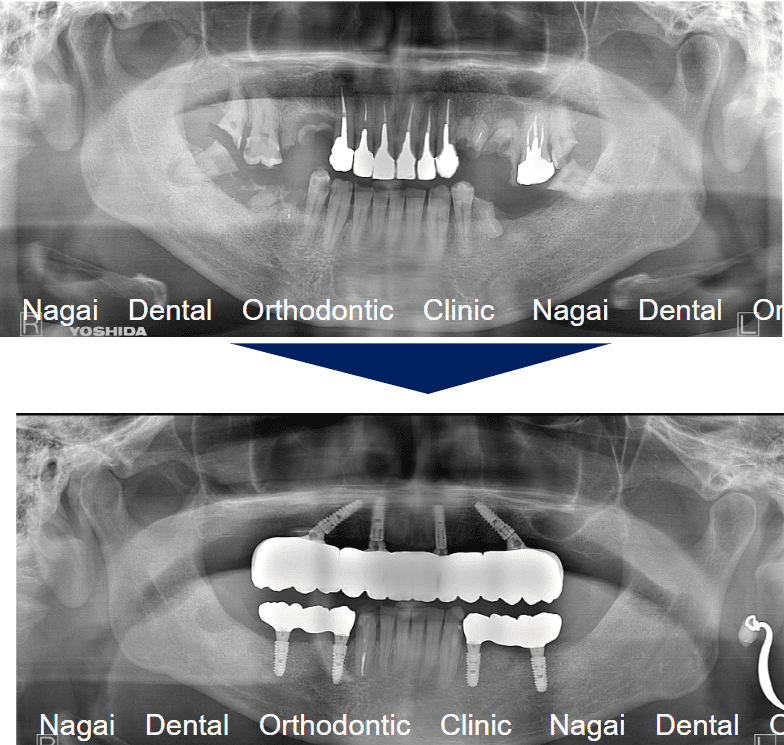

【口腔内の詳細変化】

▲再構築を目的とした治療を行いました

▲欠損していた左上奥歯部分の補綴完了状態

▲支持の安定が期待される治療を行いました

| 年齢/性別 | 70代/男性 |

| 背景 | 既存補綴物の脱離と広範囲な欠損を主訴に来院。上下顎ともに「オールオン4」を採用し、骨造成を最小限に抑えつつ即日の機能回復を図りました。チタンフレームとジルコニアに加え、歯肉部分も精巧に再現することで自然な口元を構築。安定した噛み合わせにより、食事や会話を心から楽しめる日常を取り戻されました。 |

| 治療期間 | 約16か月(通院8回) |

| 費用 | 6,357,780円(税込) |